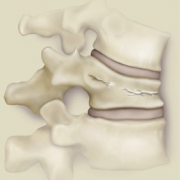

Puedes ver imágenes de una fractura y de la técnica quirúrgica de un caso real del 2015 tras este texto.